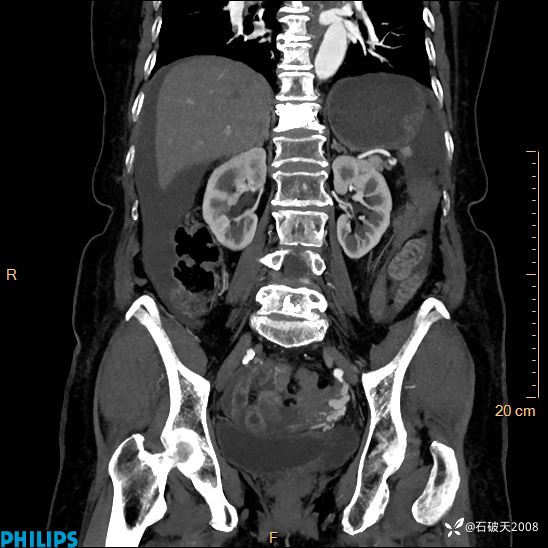

动脉期